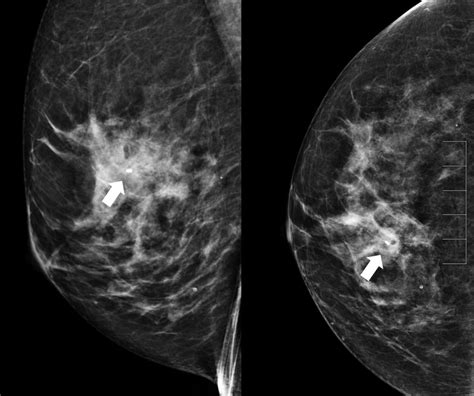

A mammogram is a specialized medical imaging procedure that uses low-dose X-rays to detect potential issues within breast tissue. Because the quality of these images is paramount for early detection, certain factors can inadvertently interfere with the clarity of the scan. These factors often stem from what you choose to wear or apply to your skin in the hours leading up to the appointment. By taking a few simple, intentional actions on the night before mammogram, you create the best possible conditions for a successful and efficient screening.

• Avoid Deodorants, Antiperspirants, and Powders: This is arguably the most critical rule. Aluminum-based ingredients in deodorants and antiperspirants, as well as minerals found in body powders, can appear as white spots on the X-ray image. These spots can look suspiciously like calcifications, potentially causing confusion for the radiologist.